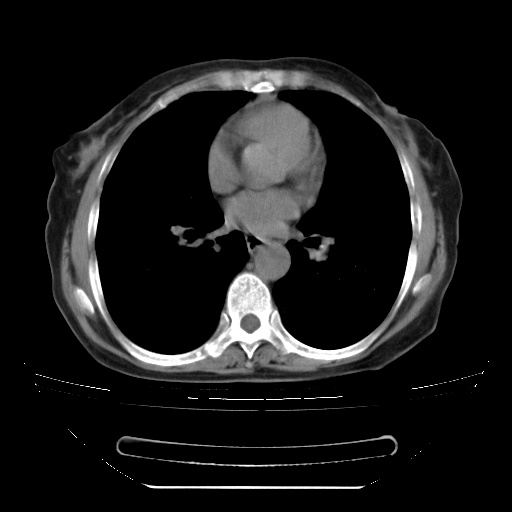

患者女性,72岁,慢性咳嗽3月余,曾抗炎治疗无效果,最近抗结核治疗约半月余,症状缓解。

ct示两肺粟粒状病灶,以两肺上叶尖后段及下叶背段分布为主;首先考虑结核。请战友们分析。

两肺内病灶呈小结节状和树芽状,纵膈的肿大的淋巴结密度不均匀,并见有钙化,考虑为两肺结核可能更大些。

两肺内病灶呈小结节状和树芽状,纵膈的肿大的淋巴结密度不均匀,并见有钙化,多形态病灶,考虑为两肺结核,肝内考虑小囊肿。

片子很好,质量很高,两侧肺门淋巴结肿大并有钙化,两肺弥漫病灶,首先考虑tb并播散,但年龄大了呀(72岁)小细胞肺癌不能除外,如果是肺癌也没什么大的治疗了,建议正规抗结核治疗后复查